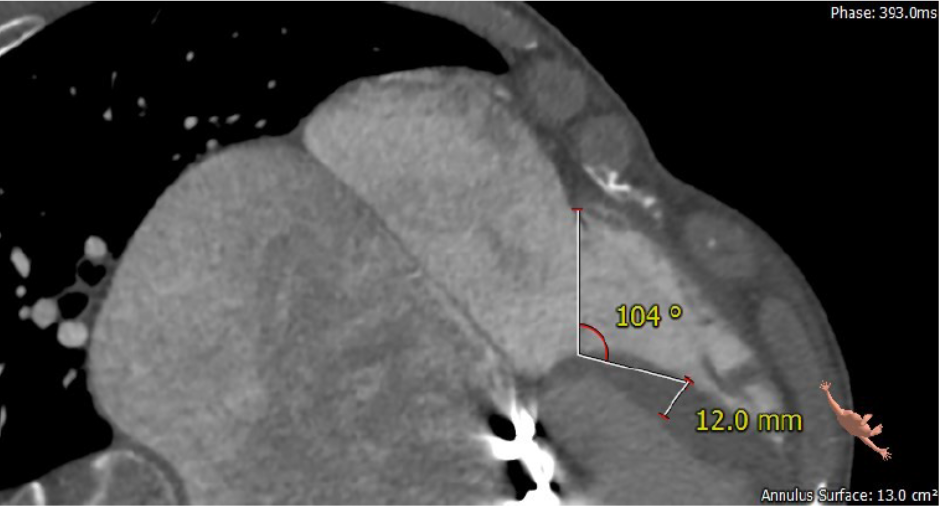

长海医院心外科徐志云、陆方林团队综合该患者CT、超声检查结果,对该患者的情况进行了充分的评估和讨论,决定采用LuX-Valve®瓣膜系统对患者进行微创治疗。手术于7月12日上午在长海医院导管室进行。根据术前CT的测量结果,选择使用JS/TTVI-30-55型号的LuX-Valve®瓣膜。只需在患者右侧第五肋间开一个小孔,经右心房穿刺,在心脏不停跳的情况下,用导管将介入瓣送入右心室,反复调整瓣膜位置,最终超声确认无瓣周漏后对瓣膜进行锚定。术后超声和造影显示瓣膜位置良好,无明显反流。

第二例患者为56岁男性,25年前接受了“主动脉瓣+二尖瓣机械瓣置换术”,约18年前出现三尖瓣关闭不全,近年来复查彩超示三尖瓣反流逐渐加重伴轻微黄疸、双下肢水肿,虽长期服用利尿剂治疗,但效果越来越差。长海医院心外科徐志云、陆方林团队综合该患者CT、超声检查结果,对该患者的情况进行了充分的评估和讨论,决定采用LuX-Valve®瓣膜系统对患者进行微创治疗。手术于7月12日下午进行,由于病人左心房扩大压迫右心房,心室游离壁距离瓣环中心仅29.8mm,再加上室间隔与瓣环夹角过大,手术操作有一定难度,瓣膜锚定也需要相当的经验。